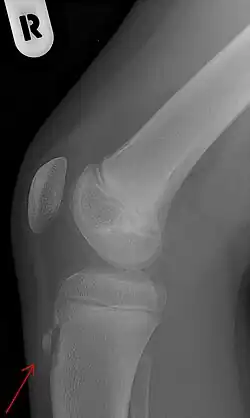

Eine Bildgebung kommt bei atypischer Symptomatik in Betracht, dann je nach Fragestellung und Differentialdiagnose Sonographie des Sehnenansatzes (DD:Bursitis, Abszess), eine Röntgenaufnahme seitlich oder selten eine Kernspintomographie. Diagnostische Kriterien sind dann Fragmentation der Tuberositas, Auftreibung der ansetzenden Sehne, Weichteilödem sowie im MRT angrenzende Ödeme in der Tibia.